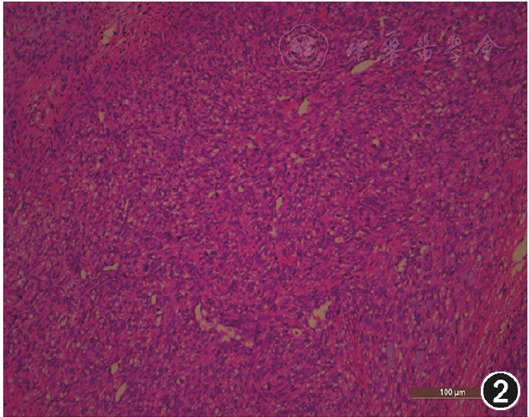

术后病理检查:肿瘤4 cm×3 cm×3 cm大小,累及输尿管壁,并可见脉管瘤栓;镜下观察见肿瘤细胞呈梭形、交错条索状排列,部分呈栅栏状、车辐状排列(图2)。诊断为左输尿管上段平滑肌肉瘤。肿瘤切缘处2枚淋巴结未见转移;左输尿管及左肾血管切缘均阴性。免疫组化染色检查:SMA、Actin、Desmin(+),S-100、Melan-A、EMA、CK、CD117、HMB45(-),Ki-67>50%(+)。术后随访6个月,无复发及远处转移。

图2.病理检查镜下观察见肿瘤细胞呈梭形、交错条索状排列,部分呈栅栏状、车辐状排列(HE ×100)